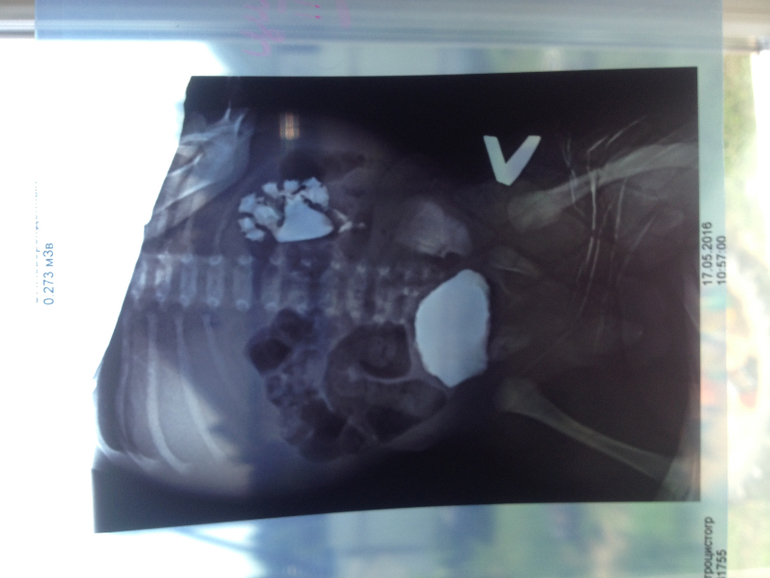

Уретрогидронефроз с ПМР 4 ст

Это результаты нашего обследования почек за 2 месяца, собираемся ехать в РДКБ г. Москва. Как считаете у нас есть шансы на сохранение почки?